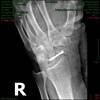

volviendo de apoco hace 10 dias que em sacaron el yeso de la muñeca por una fractura de escafoide (1 clavo) y tibia 2(clavos) hace 5 meces que no tocaba una bici